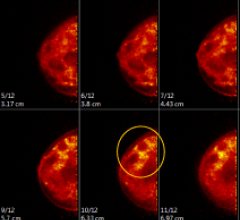

March 9, 2012 — Researchers from Boca Raton Regional Hospital in Boca Raton, Fla., showed that the FDG dose for positron emission mammography (PEM) may be reduced by up to 50 percent without impacting sensitivity.